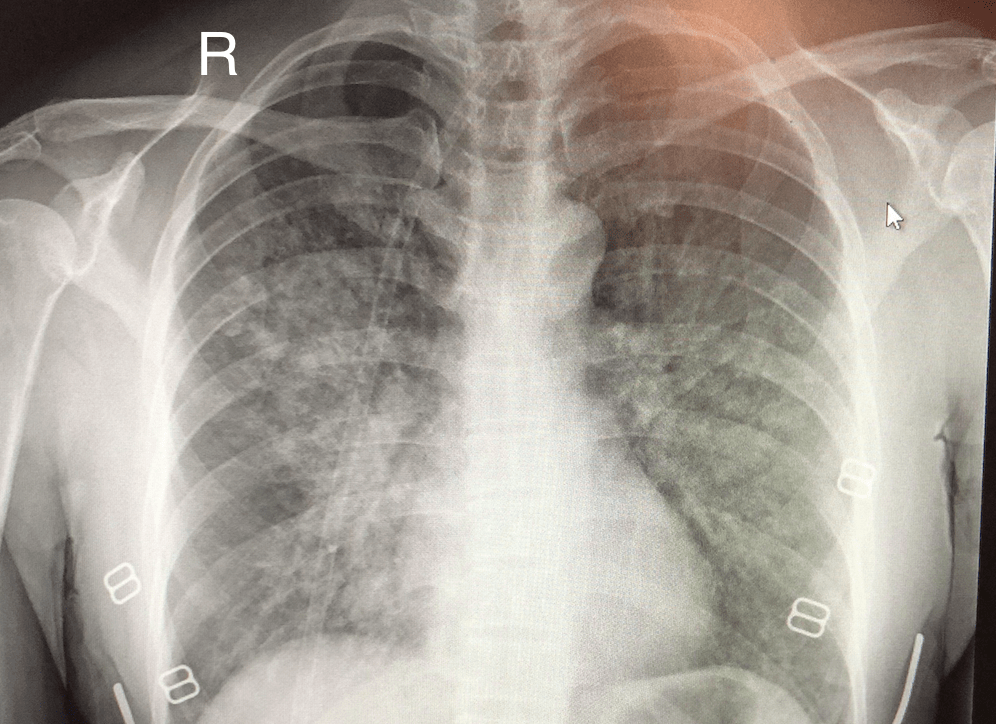

ادم ریوی ارتفاع بالا (HAPE) یک فوریت پزشکی بسیار خطرناک است که معمولاً در افرادی بروز میکند که به سرعت صعود کردهاند، و به دلیل تجمع مایعات در ریهها ایجاد میشود. این وضعیت ناشی از افزایش نفوذپذیری مویرگهای ریه در پاسخ به هیپوکسی شدید است.

علائم کلیدی HAPE شامل تنگی نفس حتی در حالت استراحت، احساس سنگینی و گرفتگی در قفسه سینه، سرفههای مکرر و مهمتر از همه، کبودی لبها (سیانوز) است. سیانوز به تغییر رنگ پوست و مخاط به آبی یا خاکستری اطلاق میشود که نشاندهنده کمبود شدید اکسیژن در خون است. در صورت مشکوک بودن به HAPE، تنها اقدام درمانی قطعی، فرود فوری به پایینترین ارتفاع ممکن است.

تیمهای پزشکی کوهستان میتوانند در شرایطی که فرود غیرممکن است، با اکسیژندرمانی فوری جان بیمار را نجات دهند، اما اشتباهترین کار در این حالت، ادامه صعود است.